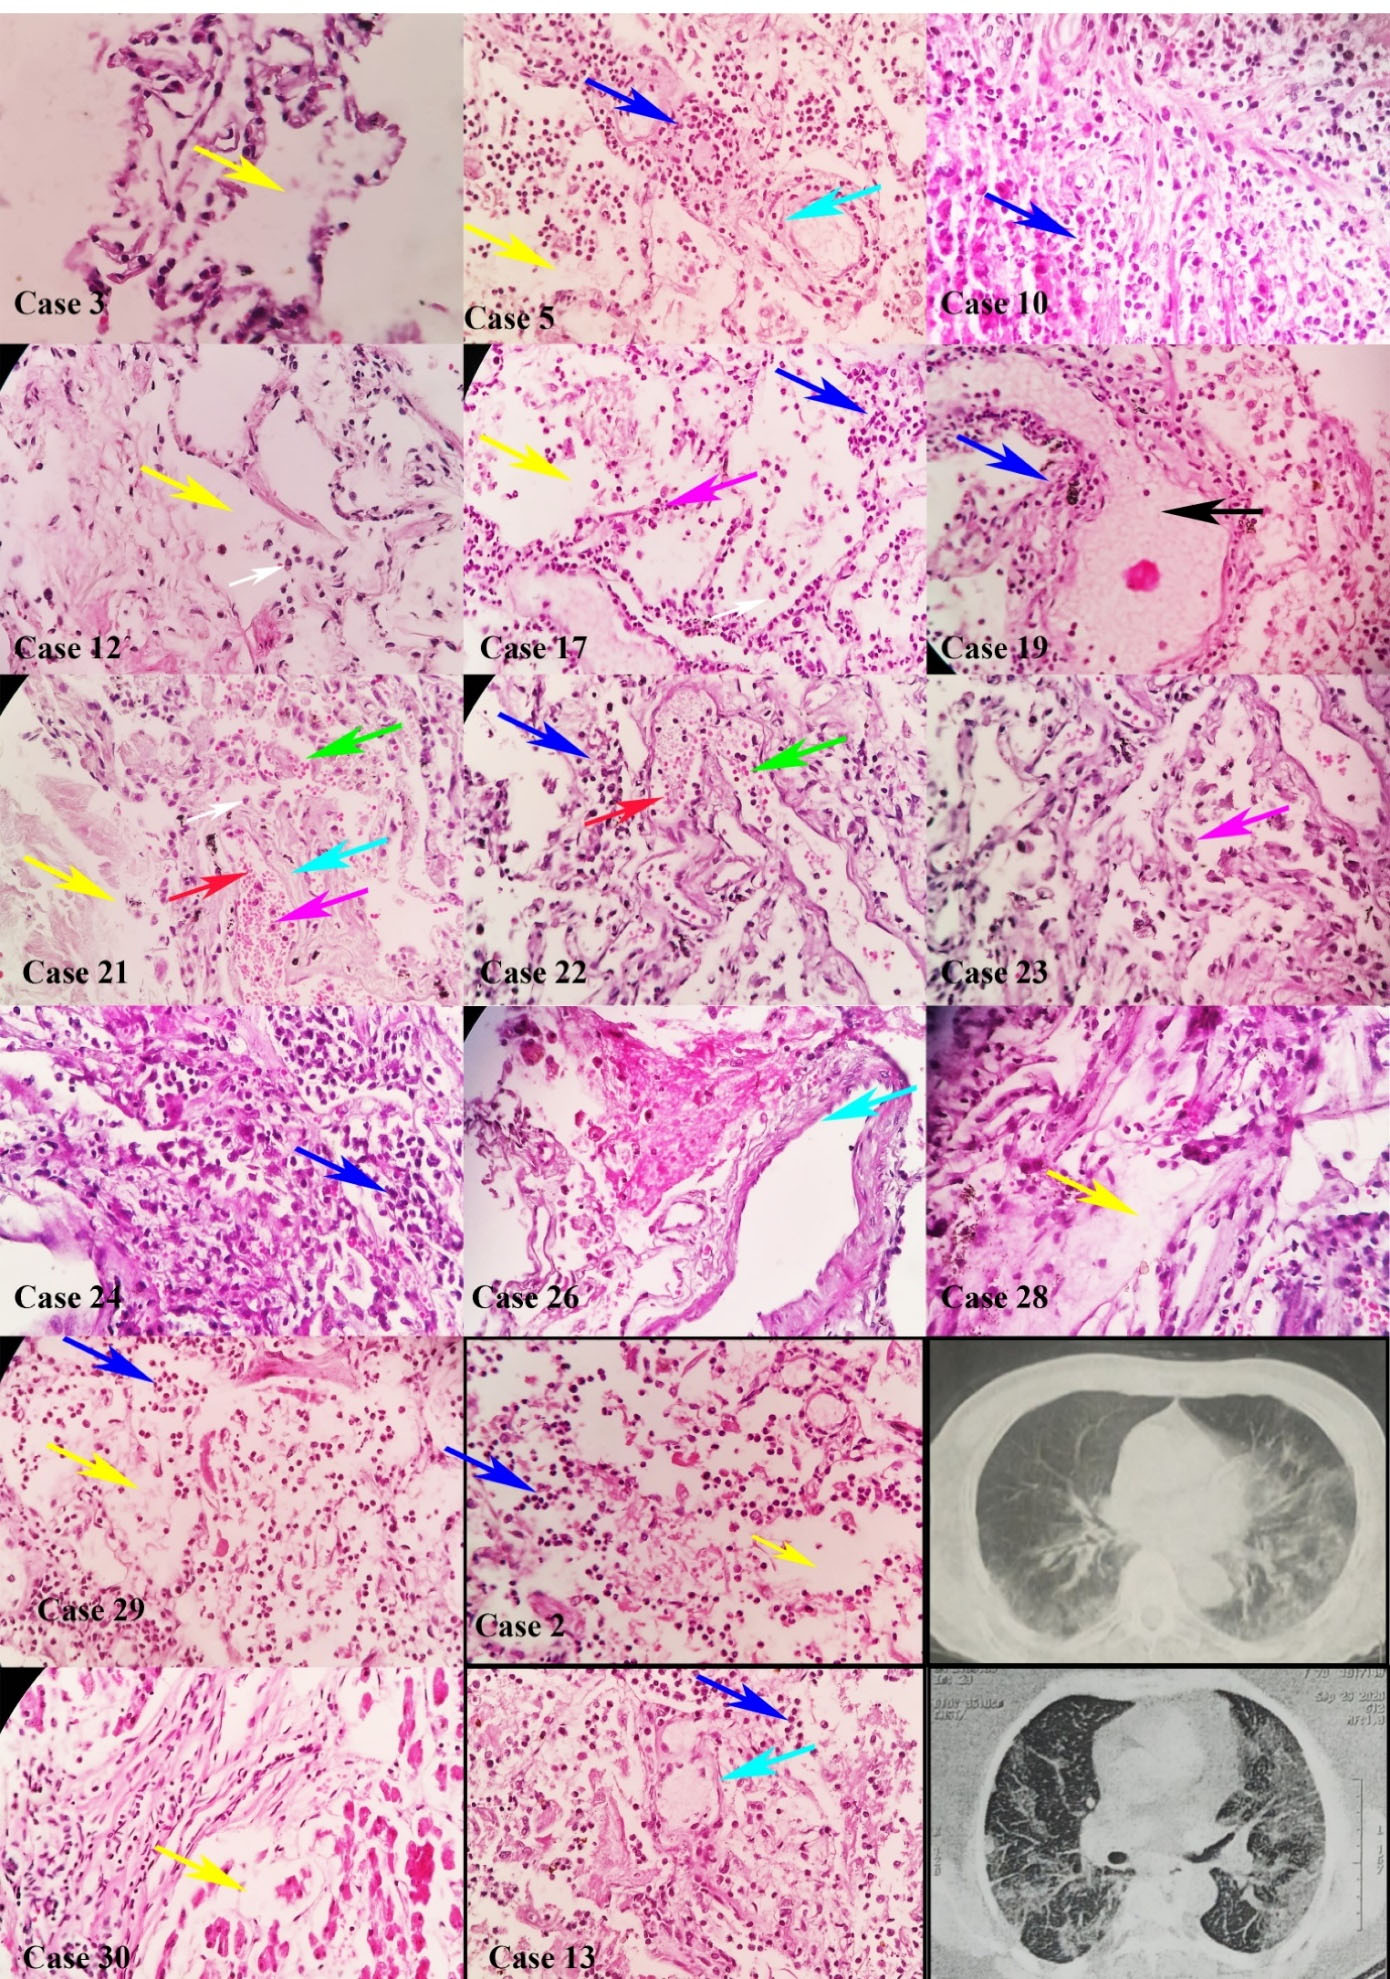

We evaluated 28 samples of pulmonary tissues. Histopathological study revealed acute exudative phase in 5 (17.9%), sub-acute proliferative phase in 16 (57.1%), and late fibrotic phase in 7 patients (25%). The most common histopathologic findings in the pulmonary tissue included DAD in 28 (100%), hyaline membrane formation in 26 (92.8%), bronchopneumonia in 20 (71%), increased number of types II pneumocytes in 14 (50%), alveolar hemorrhage in 12 (42.8%), anthracosis in 11 (39.2%), and micro-thrombosis in one (4%). DAD comprised the exudative phase in 5 (17.9%), the exudative-proliferative phase in 16 (57.1%), and the fibrotic-organizing phase in 7 samples (25%) (Figure 1, Figure S2 and Figure S3).

Figure 1.

Diffuse Alveolar Damage in Pulmonary Tissues of Deceased Patients with COVID-19. Pulmonary tissues in cases 2, 3, 5, 10, 12, 13, 17, 19, 21, 22, 23, 24, 26, 28, 29, and 30 showed diffuse alveolar damage in all tissues, consisting of edema (yellow arrow), intra-alveolar hemorrhage (red arrow), neutrophil clusters (blue arrow), plasma cells (white arrow), type II pneumocyte (magenta arrow), hyaline formation (cyan arrow), and fluid accumulation (black arrow) with hematoxylin and eosin dyes. Computed tomography in cases 2 and 13 (× 100 magnification)